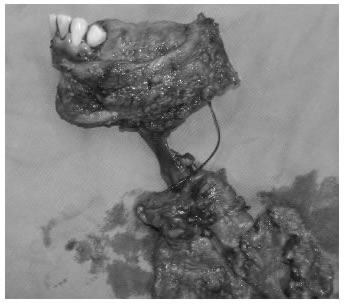

Principio 4. El primer intento del tratamiento debe ser curativo.

Una característica que diferencia a los cirujanos oncólogos de los no oncólogos es el nihilismo terapéutico de estos últimos. En un paciente con cáncer, el primer intento de tratamiento debe ser el mejor y el definitivo, y por lo tanto, la magnitud de la resección o los efectos adversos no son una limitación absoluta. Lo importante para ofrecer una cirugía con carácter oncológico, es actuar con proporcionalidad, la cual muchas veces es difícil de establecer. La mejor forma de saber si se es proporcional, siguiendo las premisas éticas, es hacer el ejercicio mental de lo que se va a lograr con el procedimiento, con el cual debe cumplirse, como mínimo, con uno de los tres siguientes objetivos: curación, aumento de la supervivencia con el menor deterioro en la calidad de vida o algún grado de alivio sintomático. Si con el procedimiento propuesto no se cumple ninguno de estos objetivos, se considera una medida fútil y, por consiguiente, éticamente inaceptable. Si se alcanza, como mínimo, el objetivo de dar algún grado de alivio sintomático, esto es, que el paciente va a estar mejor con el procedimiento que sin él, se está conminado a practicar dicho procedimiento por más mutilante que parezca, máxime, si se hace con intención curativa. Es así como, en muchas ocasiones, se justifican procedimientos como una hemipelvectomía, aun con fines higiénicos y paliativos (figura 3).